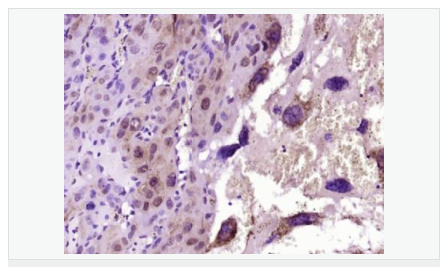

| 產(chǎn)品應(yīng)用 | WB=1:500-2000 IHC-P=1:100-500 IHC-F=1:100-500 Flow-Cyt=1ug/Test ICC=1:100-500 IF=1:100-500 (石蠟切片需做抗原修復(fù)) not yet tested in other applications. optimal dilutions/concentrations should be determined by the end user. |

| 細胞定位 | 細胞核 細胞漿 細胞膜 線粒體 |